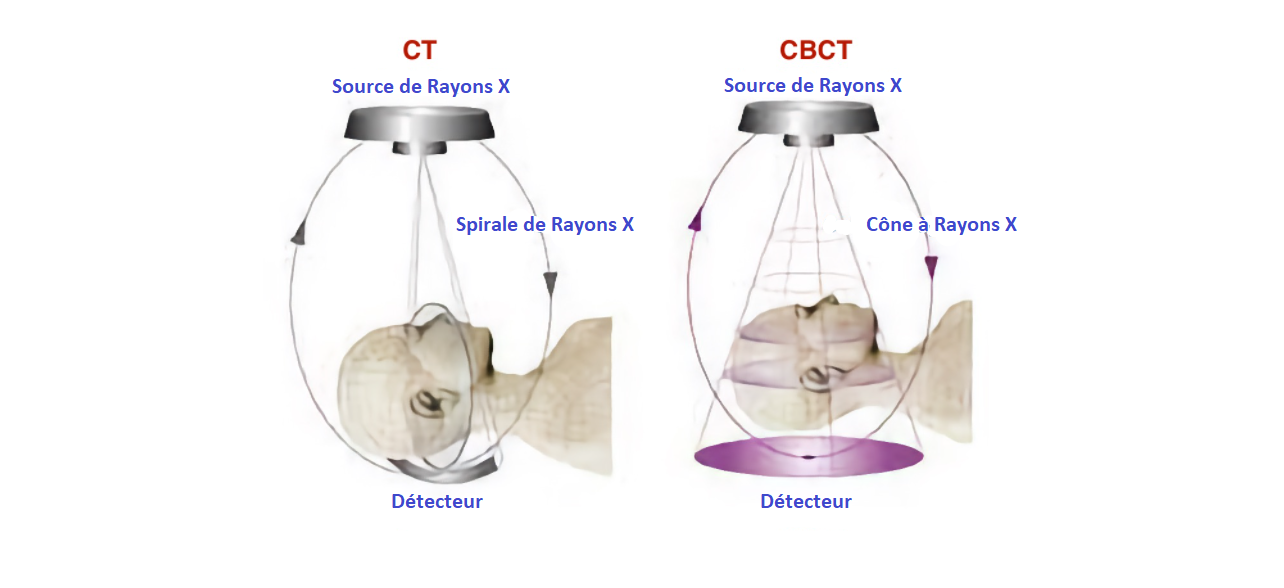

Quelle est la différence entre la tomographie informatisée conventionnelle (TC) et la tomographie informatisée à faisceau conique (CBCT) ?

La technologie TC a été développée en 1967 par Sir Godfrey Hounsfield. Cette technologie est basée sur la capture d'images, par des écrans détecteurs, de multiples plans jusqu'à l'obtention d'une image complète. Cette technique implique davantage de radiation pour le patient. Les images obtenues sont utiles pour traiter les traumatismes maxillo-faciaux, la pathologie buccale ou encore la pathologie des glandes salivaires. Cette technologie est aussi utilisée pour la planification des implants dentaires et les études de croissance et de développement.

Contrairement à l'imagerie TC, l'imagerie CBCT permet d'obtenir le volume tridimensionnel des données en un seul balayage au cours duquel le capteur 2D et la source de rayonnement tournent de manière synchrone autour de la tête du patient sur 180° ou 360° selon l'équipement CBCT utilisé.